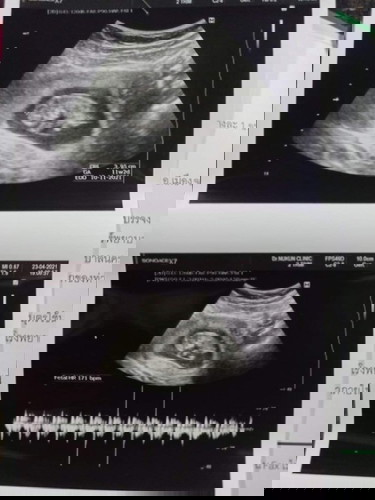

ประจำเดือนมาล่าสุด22-25ก.พ ในขณะที่ทานยาคุมยังไม่หมดแผง และในเดือนมี.ค ทานยาคุมแผงใหม่ปกติ แต่รู้สึกแปลกที่ร่างกาย ท้องผูกเอย อ้วกเอย และประจำเดือนมาจิ๊ดนึง เปื้อน กกน. และหายไป เลยซื้อที่ตรวจมาตรวจ ขึ้น2ขีดชัดมาก พอมาหาหมอ ตอนประมาน23 เมษา หมอบอกว่า ท้องได้11w6dแล้ว จะเข้า3เดือนแล้ว ต้องเชื่อตามประจำเดือนหรือเครื่องอัลตาซาวคะแม่ๆ แต่น้องก็ตัวใหญ่นะคะ